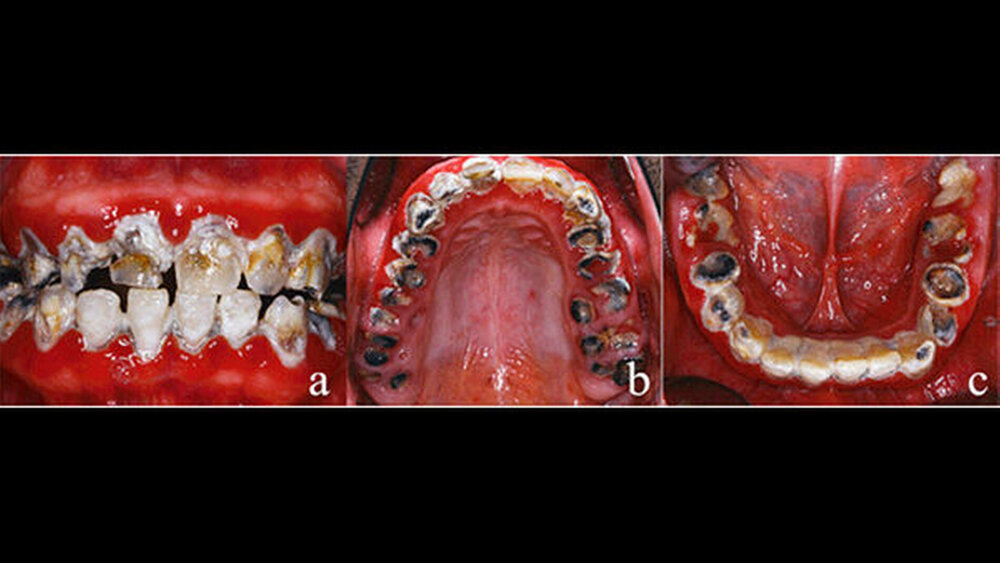

Dem Beginn der zu diesem Zeitpunkt erforderlichen Therapie war eine achtjährige Zahnarztabstinenz und eine damit einhergehende starke Vernachlässigung der Mundhygiene vorausgegangen (Abbildungen 1a-c). Als Grund für die lange Zahnarztabstinenz gab der Patient eine Zahnarztphobie an. Sein äußeres Erscheinungsbild war durchaus gepflegt und stand somit nicht im Einklang mit der oralen Situation. Eine Begründung, warum es zu dem offensichtlich desaströsen Zustand seiner Bezahnung gekommen war, konnte oder wollte der Patient nicht äußern. Die Reaktionen waren auf Nachfrage eher ausweichend und nichtssagend. Der Patient kann als gut situiert bezeichnet werden. Er trat eher introvertiert auf und verbarg seine Zähne beim Reden durch die Lippe.

Der allgemeinzahnmedizinische Befund zeigte ein generalisiert-kariöses Gebiss mit vollständig zerstörten Zähnen im Seitenzahnbereich (Abbildungen 1a-c). Die Zähne 13, 21, 22, 33–43 reagierten beim CO2-Sensibilitätstest positiv. Die restlichen Zähne im Ober- und Unterkiefer zeigten bei Vitalitätsprüfung keine Reaktion. Die Sondierungstiefen lagen im Frontzahngebiet von Ober- und Unterkiefer bei 3–4 mm sowie im Seitenzahnbereich bei größer/gleich 5 mm. Die Ober- und Unterkieferfrontzähne wiesen – im Gegensatz zum Seitenzahnbereich – keine erhöhten Lockerungsgrade auf.